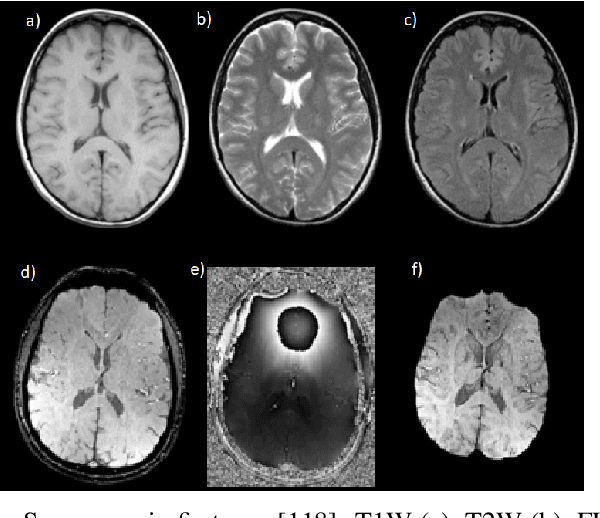

Abstract:Cerebral microbleeds detection is an important and challenging task. With the gaining popularity of the MRI, the ability to detect cerebral microbleeds also raises. Unfortunately, for radiologists, it is a time-consuming and laborious procedure. For this reason, various solutions to automate this process have been proposed for several years, but none of them is currently used in medical practice. In this context, the need to systematize the existing knowledge and best practices has been recognized as a factor facilitating the imminent synthesis of a real CMBs detection system practically applicable in medicine. To the best of our knowledge, all available publications regarding automatic cerebral microbleeds detection have been gathered, described, and assessed in this paper in order to distinguish the current research state and provide a starting point for future studies.